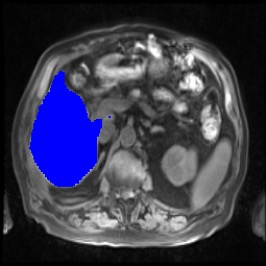

Integrating high-level semantically correlated contents and low-level anatomical features is of central importance in medical image segmentation. Towards this end, recent deep learning-based medical segmentation methods have shown great promise in better modeling such information. However, convolution operators for medical segmentation typically operate on regular grids, which inherently blur the high-frequency regions, i.e., boundary regions. In this work, we propose MORSE, a generic implicit neural rendering framework designed at an anatomical level to assist learning in medical image segmentation. Our method is motivated by the fact that implicit neural representation has been shown to be more effective in fitting complex signals and solving computer graphics problems than discrete grid-based representation. The core of our approach is to formulate medical image segmentation as a rendering problem in an end-to-end manner. Specifically, we continuously align the coarse segmentation prediction with the ambiguous coordinate-based point representations and aggregate these features to adaptively refine the boundary region. To parallelly optimize multi-scale pixel-level features, we leverage the idea from Mixture-of-Expert (MoE) to design and train our MORSE with a stochastic gating mechanism. Our experiments demonstrate that MORSE can work well with different medical segmentation backbones, consistently achieving competitive performance improvements in both 2D and 3D supervised medical segmentation methods. We also theoretically analyze the superiority of MORSE.